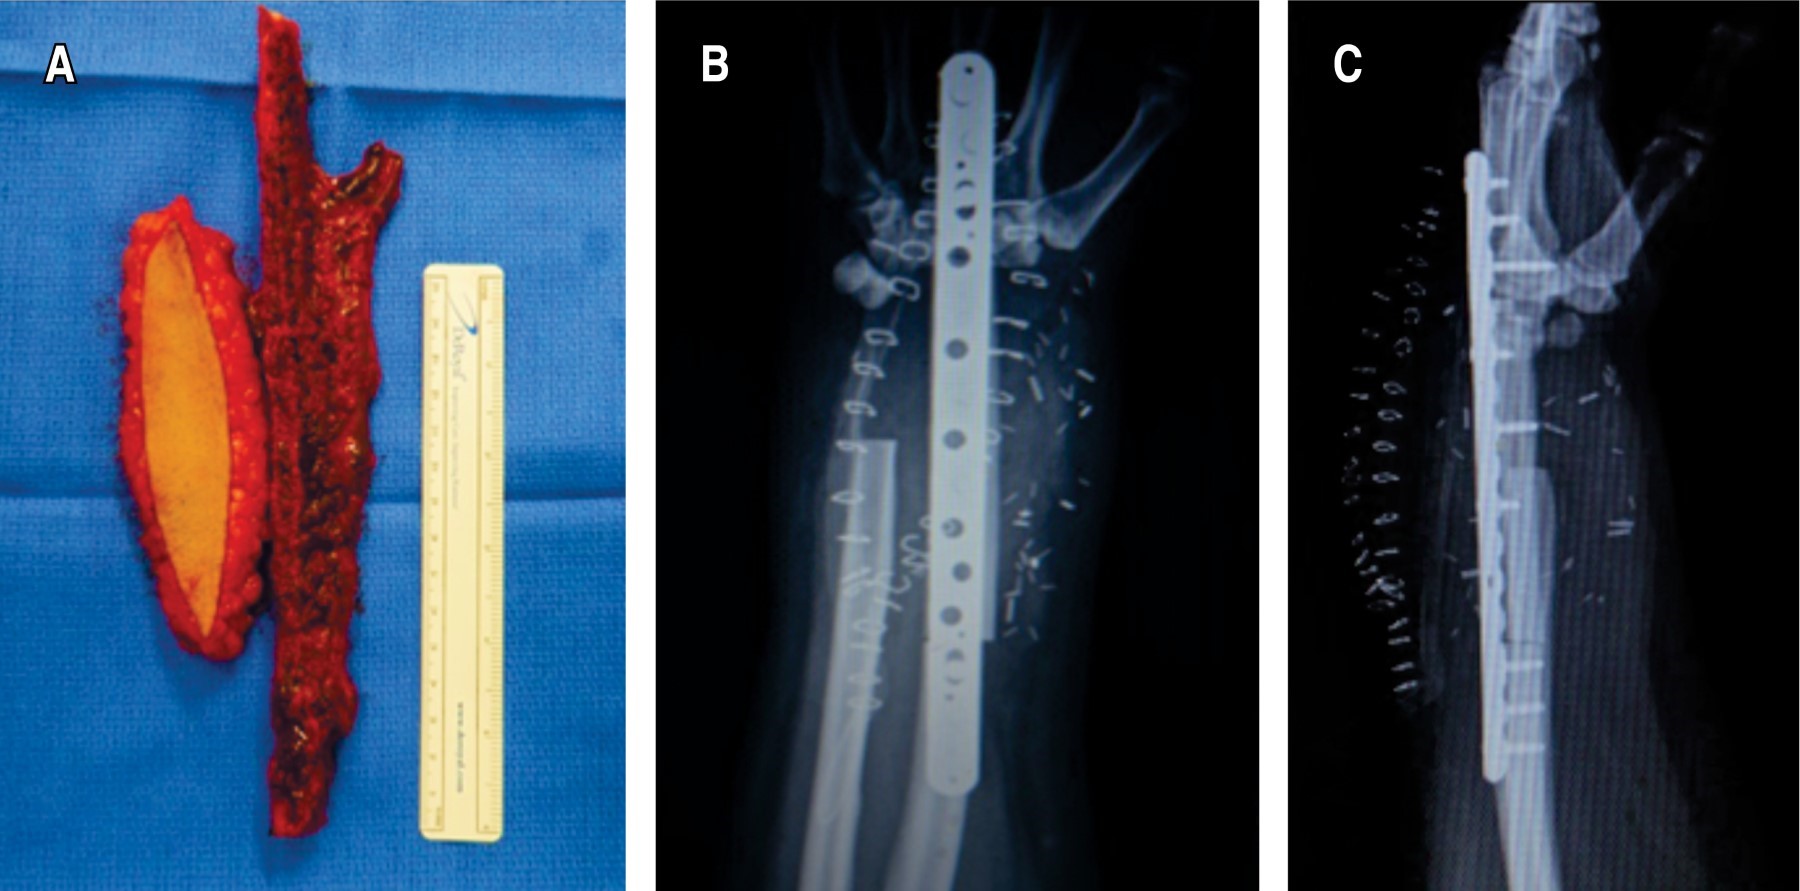

Presentamos el caso de una mujer de 45 años, sin antecedentes crónico degenerativos de importancia, que acude por presentar dolor en muñeca izquierda, con el antecedente de una fractura patológica de radio distal izquierdo en septiembre de 2018, tratada con reducción abierta y fijación interna con placa de radio distal volar y matriz ósea, actualmente consolidada. De inicio se realizó radiografía posteroanterior y lateral de la muñeca observando una lesión neoplásica en radio distal compatible con un tumor de células gigantes en un estadio III de la clasificación de Campanacci (Figura 1), se complementó el protocolo de estudio con tomografía de tórax descartando metástasis pulmonares y posteriormente se decidió como tratamiento la resección en bloque (Figura 2) (5 cm a la superficie articular proximal tanto de radio como de cúbito y se incluyó la fila proximal del carpo, todo a través de un abordaje dorsal) y reconstrucción inmediata con peroné vascularizado y artrodesis de muñeca con una placa de compresión bloqueada (Figura 3).

El procedimiento quirúrgico consistió en la colocación de un colgajo vascularizado perióstico cubital pediculado (CVPCP) proveniente de la arteria interósea anterior, para el cual, la paciente se colocó en decúbito supino, con torniquete a nivel del brazo, se utilizó el mismo abordaje dorsal realizado en la cirugía previa, se expusieron ambas zonas de no unión, se realizó debridación de los bordes escleróticos y se colocó injerto de cresta iliaca, tomado con la técnica convencional en la no unión distal entre el peroné y el hueso grande. Posteriormente, a través del mismo abordaje se abrió la membrana interósea, se refirió y se disecó la arteria interósea anterior, 16 cm distal al codo sobre el margen del flexor digital profundo y el flexor largo del pulgar, se diseñó el colgajo perióstico de forma rectangular sobre la superficie dorso-radial del cúbito de 4 cm de largo por 2 cm de ancho y se disecó con un elevador de periostio junto con los ramos provenientes de la interósea anterior, se colocó sobre su eje longitudinal envolviendo el sitio de no unión proximal y se suturó con prolene vascular 3-0 (Figura 5).